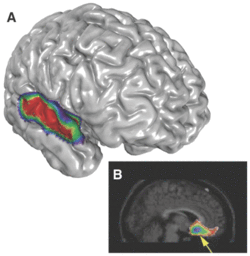

It is easy to imagine that rhythm was a very early form of musical expression. Anyone can pick up a stick, and rhythmically beat it against something. A universal human reaction is a synchronized motor response; foot tapping or other body movements. This appears to be (almost) a uniquely human trait. Sacks quotes Aniruddh Patel: "there is not a single report of an animal being trained to tap, peck, or move in synchrony with an auditory beat." However the Patel video I reference shows a bird that he now believes really is dancing. This linking of auditory and motor systems depends on interactions between the auditory and the dorsal premotor cortex, and only the human brain (or perhaps the birdbrain as well) has a functional connection between these areas. Patel goes on to argue that rhythm ".. cannot be explained as a by-product of linguistic rhythm" and must have evolved separately from speech.Rhythm can have a amazing unifying effect on a group of people. Anybody who has heard Stevie Wonder's rendition of "Fingertips," and the electrifying effect it had on the crowd, is aware of this. My son frequently participates in drum circles, and I vividly remember an experience I had many years ago in Yosemite National Park. A bunch of us were in a meadow, making random noises on various kinds of percussion instruments. After a few minutes somehow a unifying rhythm emerged. Everyone tuned into it and played ecstatically. I totally lost my sense of "I" and for a few fleeting minutes a ragtag mob became a single throbbing organism. A few other times in my life I have had a transcendent experience dancing to very loud, very rhythmic music, and it was intimately connected with the fact that I was one member of a group caught up in the same frenzy.